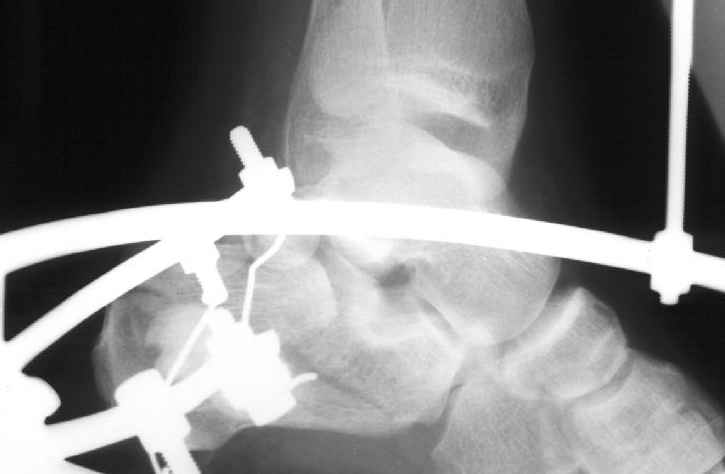

В/суставные переломы пяточной кости у молодых являются показанием к оперативной коррекции, Большой материал накоплен у д-ра Дрягина (Челябинск). В нашем отделении предпочтение отдаем открытой репозиции, при наличии выраженного отека, фликтен и т.д.

Накладываем спицевой дистрактор, позволяющий выхаживать м/ткани и одновременно устранять захождение отломков.

Окончательная фиксация спицами, пяточными пластинами (5) , в последнее время стали применять крючковидные пластины (ДЕОСТ) (6,6a).

Учитывая сроки после травмы, я бы 1 этапом наложил дистакционный аппарат(будут трудности при одновременном восстановлении длины пятки, кроме того не надо забывать о возможных краевых некрозах). Удачи.